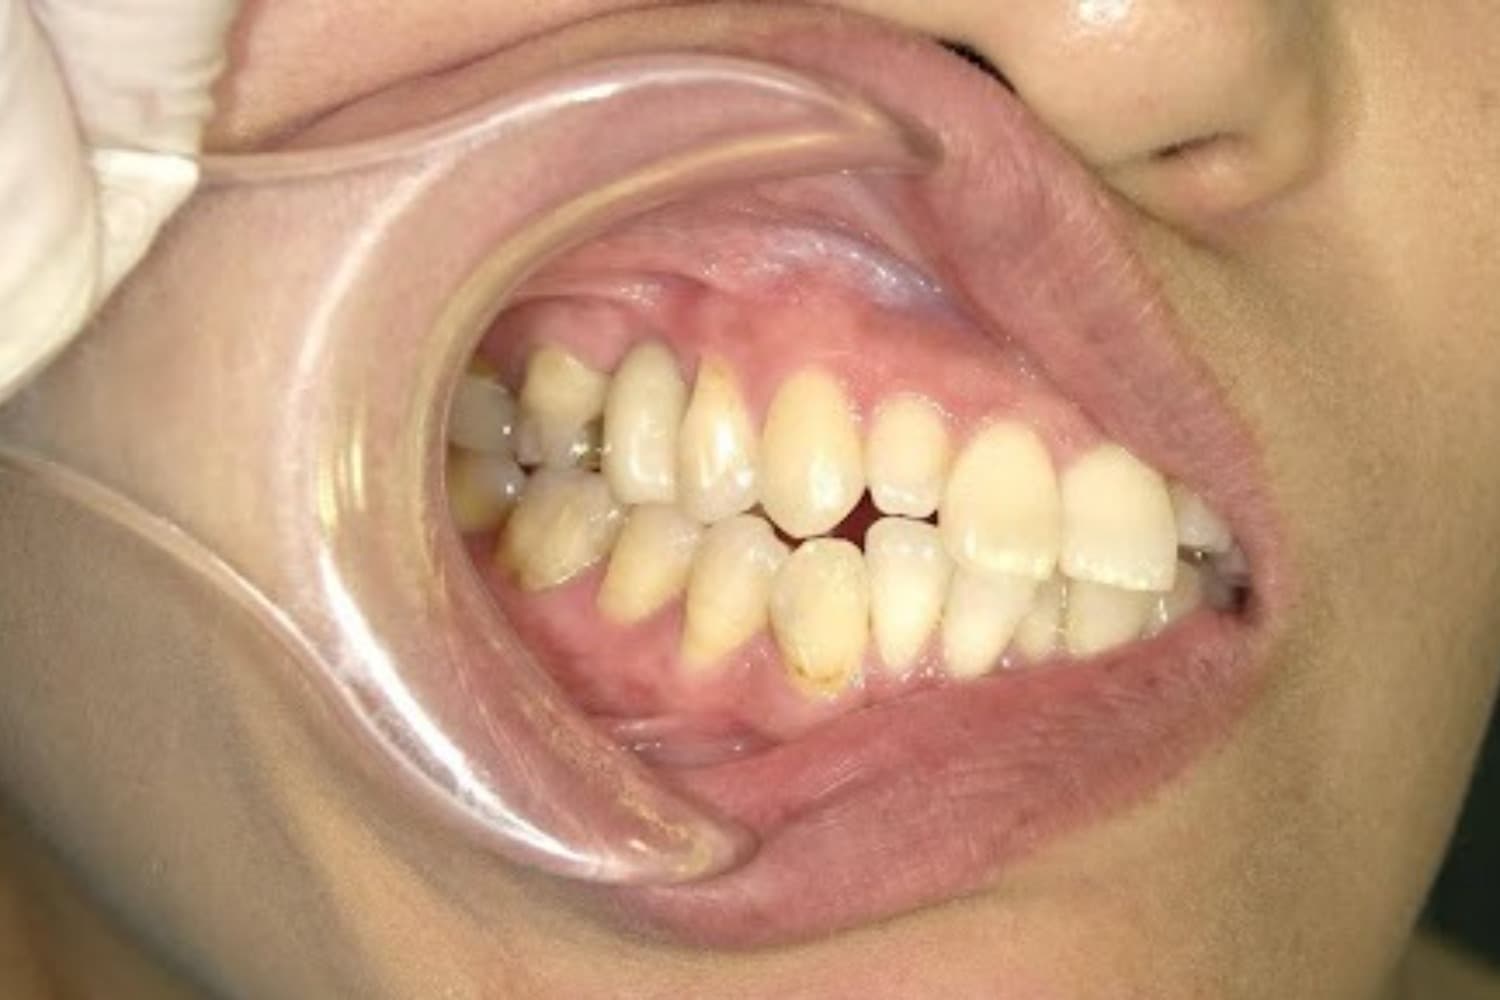

歯根破折した前歯のインプラント治療(30代男性)

Before

外傷によって歯根破折した前歯を抜歯してインプラント治療をおこなう(当日に仮歯の装着までおこなう)。

年齢

30代

性別

男性

主訴

外傷によって歯根破折している。

治療期間

2ヵ月半

治療回数

6回

費用

385000円(税込) 費用の内訳: 【インプラント基本料】330000円(税込み) 基本料金に以下を含む ・フィックスチャー及び手術費用 ・投薬費用、 ・レントゲン費用 ・インプラント上部費用(アバットメントおよびジルコニアクラウンの費用用) 【オプション費用】 ・抜歯即時埋入・即時負荷加算(プロビショナルレストレーション費用・人工骨費用・暫間アバットメント費用・抜歯費用を含む)55000円(税込)

副作用・リスク

・手術後に痛み・腫れ・出血・合併症等を引き起こす恐れがあります。 ・噛む感覚がご自身の歯と異なることがあります。 ・見た目がご自身の歯と異なる場合があります。 ・手術後もメインテナンスを続けないと、インプラントが抜け落ちてしまう恐れがあります。